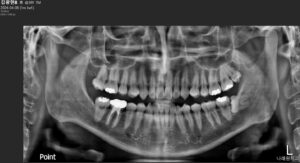

정밀한 검사를 위해

파노라마 사진을 촬영해 보았더니

아래턱 왼쪽 사랑니(#38)는

완전 매복 상태로

잇몸뼈 속에 묻혀

바로 앞의 두 번째 큰 어금니(#37)의

뿌리를 자극하고 있었습니다.

위턱 왼쪽 사랑니(#28)는

정상적으로 맹출은 하였지만

안쪽에 위치해 있다 보니

위생관리가 잘되지 않고 있었는데요.